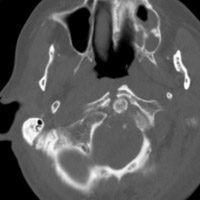

- Click on the image for a larger versionDAxial CT. This image depicts the severe fracture of the anterior arch of C1.